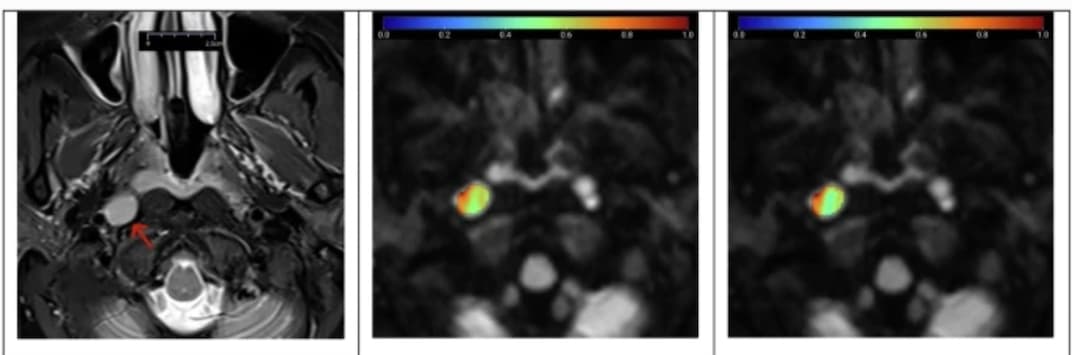

La tractographie par IRM devient un outil pertinent pour évaluer les flux dans les faisceaux de fibres cérébrales. Une étude italienne publiée dans la Revue European Radiology explore la complexité du faisceau cingulaire par tractographie probabiliste et expérimente plusieurs protocoles d’acquisitio...